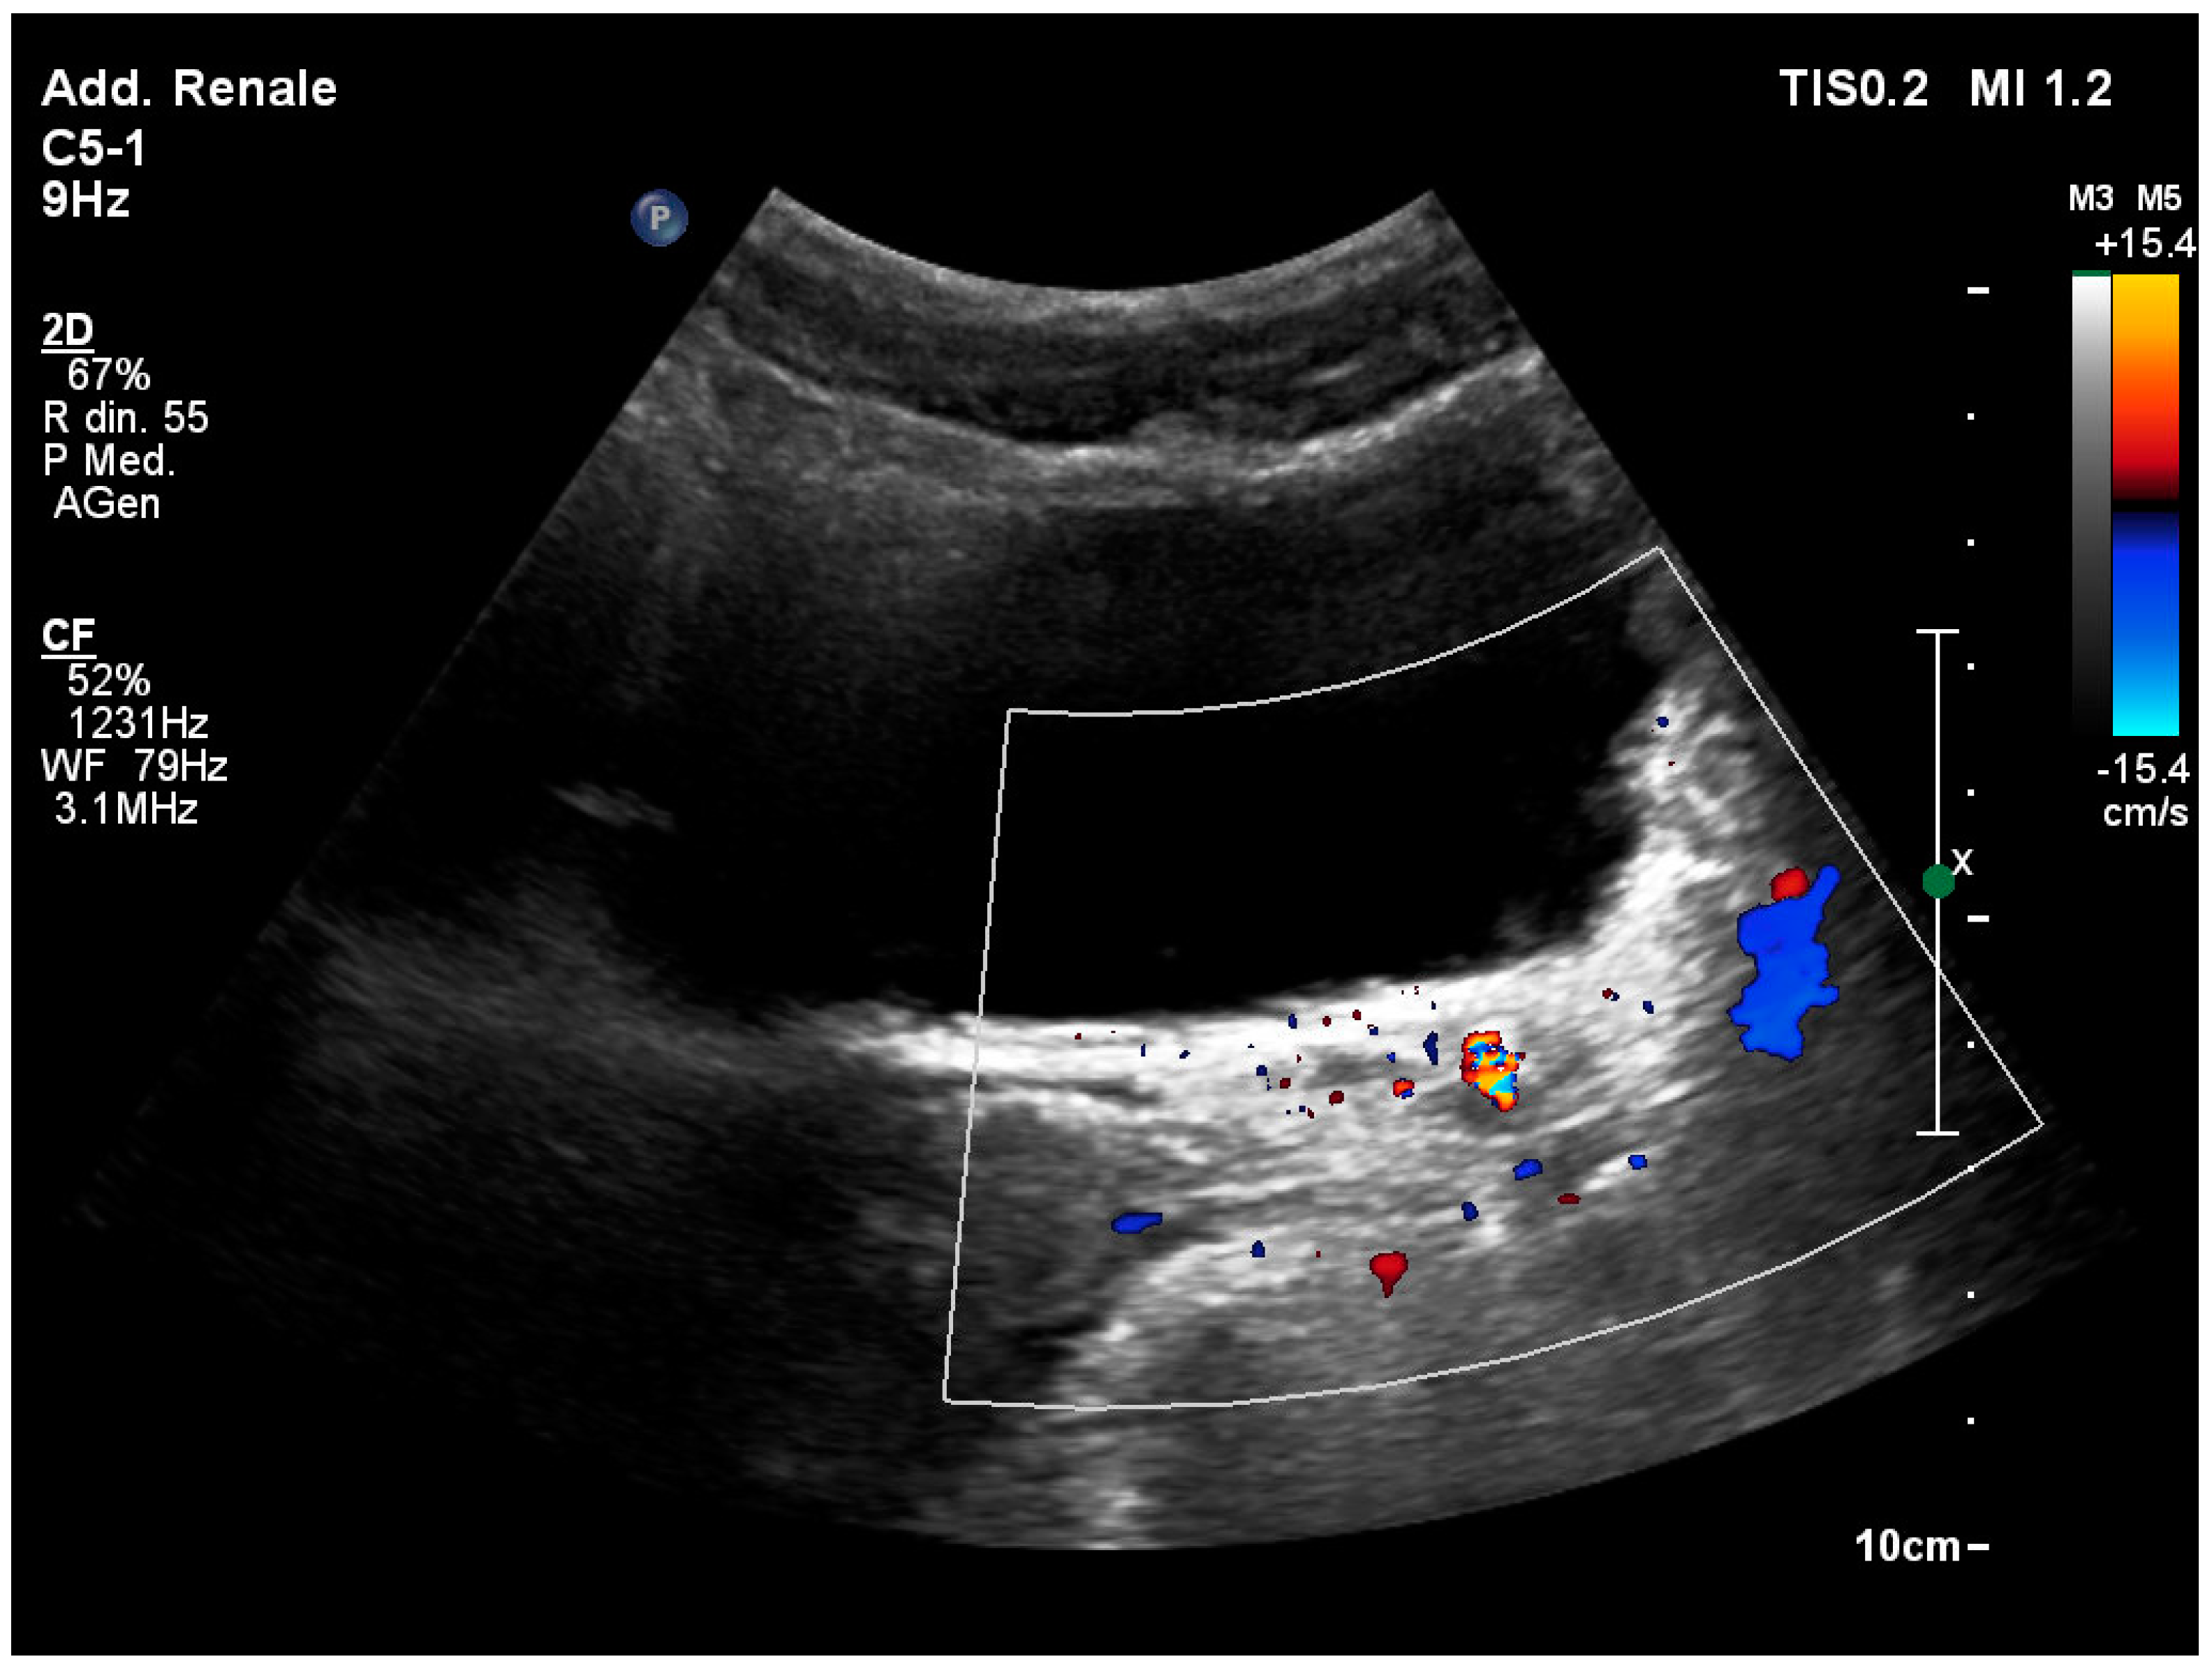

3.5. The “Twinkling” Artifact

3.6. The “Swinging Kidney” Sign

3.7. Identification of the Ureteral Jet